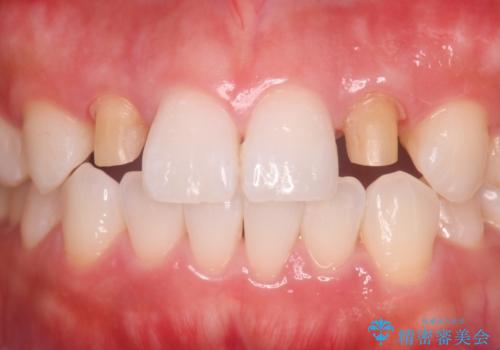

- 食べ物が歯間にはさまることを主訴に来院された患者様です。レントゲンより上顎両側切歯に根管治療が実施されていますが、被せ物が入っておらず、充填物に劣化像もみられました。歯の色の差も気にされていたのでオールセラミッククラウンにて治療いたしました。

より歯の色をきれいに見せたいという希望があったため、ホワイトニングも実施いたしました。食べ物の詰まりも改善し、きれいな仕上がりになったので非常に満足いただけました。